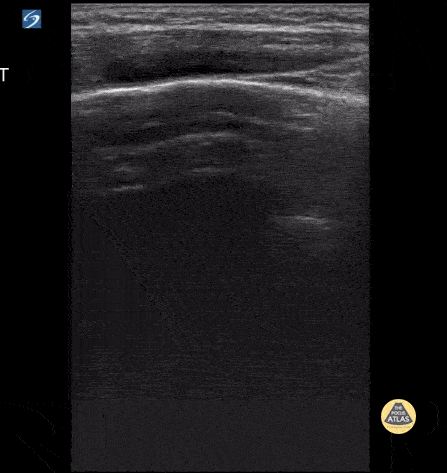

Peds-Lung - Normal Lung Sliding with Comet Tails

4 y/o with asthma who presents in respiratory distress. Using the linear probe, normal lung sliding is seen with comet tails. Contributor: Kathryn Pade, MD, Rady Children's Hospital San Diego